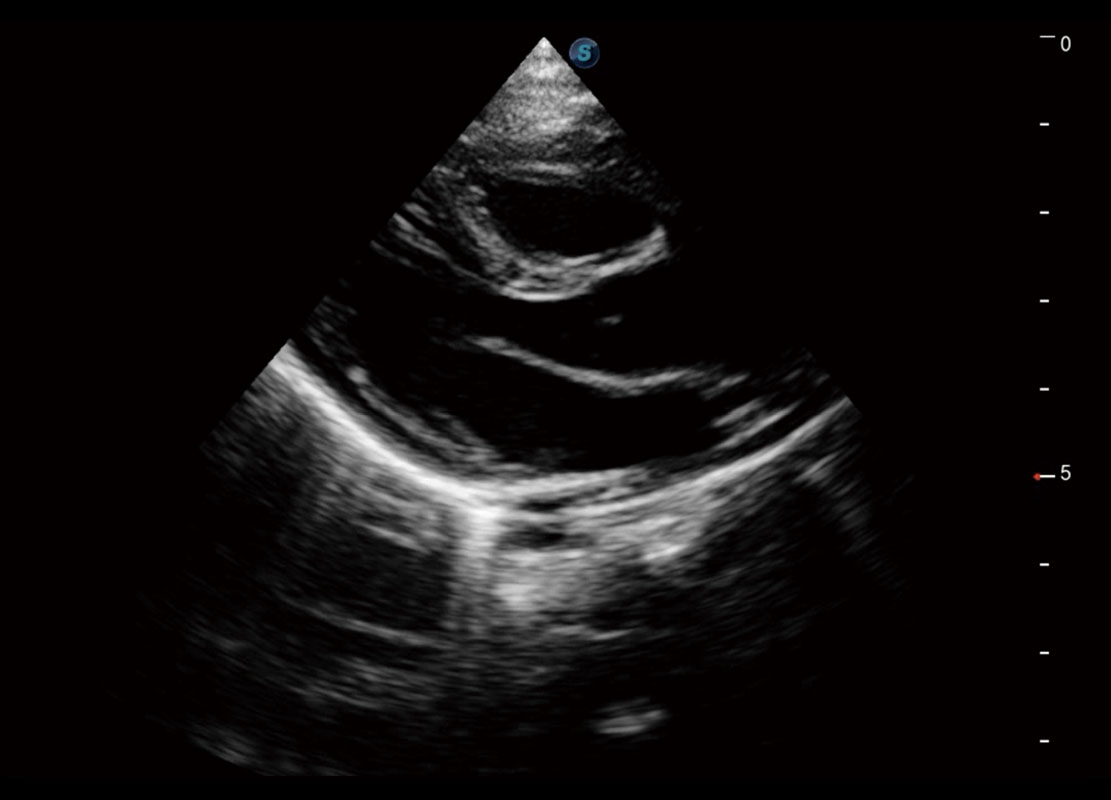

P60搭載一系列胎兒心臟成像技術(shù),實(shí)現(xiàn)精細(xì)的胎兒心臟評(píng)估。

四腔切面